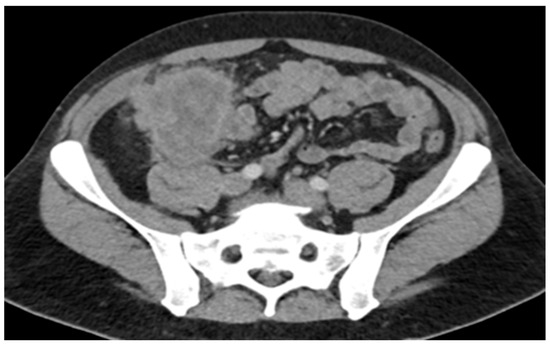

Comprehensive molecular profiling of the resected tumor was performed. The results showed a high tumor mutational burden (TMB) of 87.9 mutations/megabase, microsatellite stability, POLE mutation, BRAF p.D594G mutation, and PIK3CA p.R88Q missense mutation. Based on the presence of metastatic disease, the patient was started on first-line systemic chemotherapy with FOLFOXIRI plus Bevacizumab, in accordance with standard treatment guidelines. After three cycles, clinical and radiographic assessment revealed disease progression, evidenced by worsening abdominal pain, rising CEA levels (145.7), and an interval increase in the hepatic metastatic burden on imaging (Figure 4).

Figure 4. CT of abdomen/pelvis just before ICI: increased size of hepatic metastases, splenomegaly, and unchanged prominent left para-aortic lymph nodes; no evidence of metastatic disease in chest.